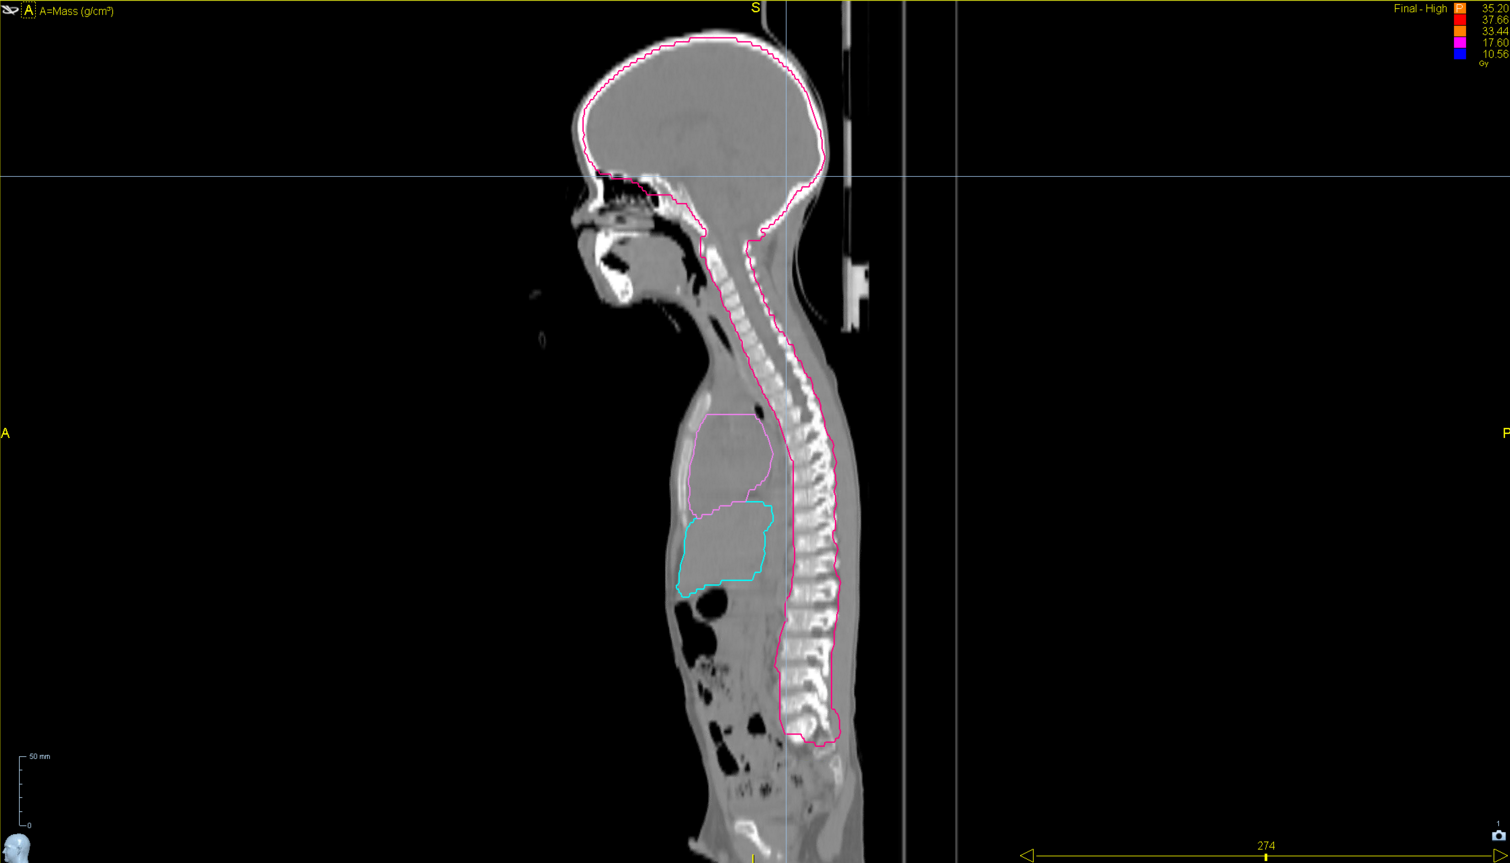

< View All Plan Studies RADIXACT SYSTEM TMI Case History AGE: 76-year-oldGENDER: Male Medical History Immidiate tolerance: Grade II dermatitis with eyelid edema, Grade I conjunctivitis resolved with Sterdex Diagnosis: Squamous cell carcinoma of the right lower eyelid Planning CT Images Treatment Plan Images ClearRT® Images Treatment Planning Highlights Fractionation